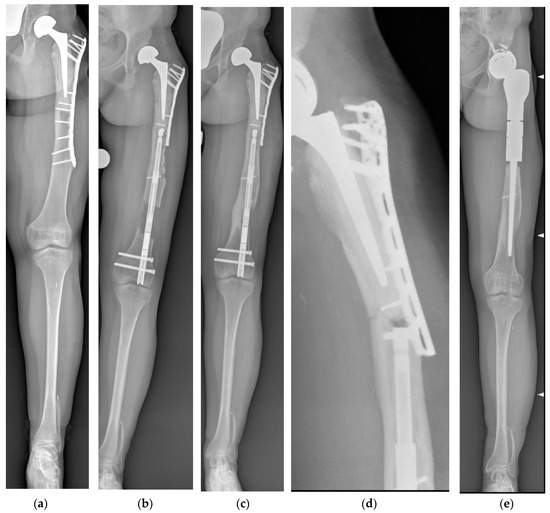

| Femur (A) | 13/M | Femoral intercalary reconstruction for OS | 52 | 49 | 15 | Yes |

| Femur (A) | 18/M | Femoral intercalary reconstruction for OS | 70 | 60 | 28 | Yes |

| Femur (R) | 20/M | Femoral intercalary reconstruction for ES | 70 | 70 | 12 | Yes |